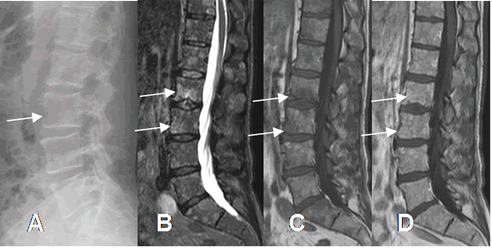

Fig 27. Mieloma múltiple.

A: Rx lateral de columna. Pérdida de la cortical anterior de L3.

B: RM sagital en STIR y C: RM sagital en T1. Múltiples áreas hiperintensas en STIR e hipointensas en T1 en todos los cuerpos vertebrales, las mas grandes en L3 y L4.

D: RM Sagital en T1 con contraste. Realce del contraste en todas las lesiones focales.